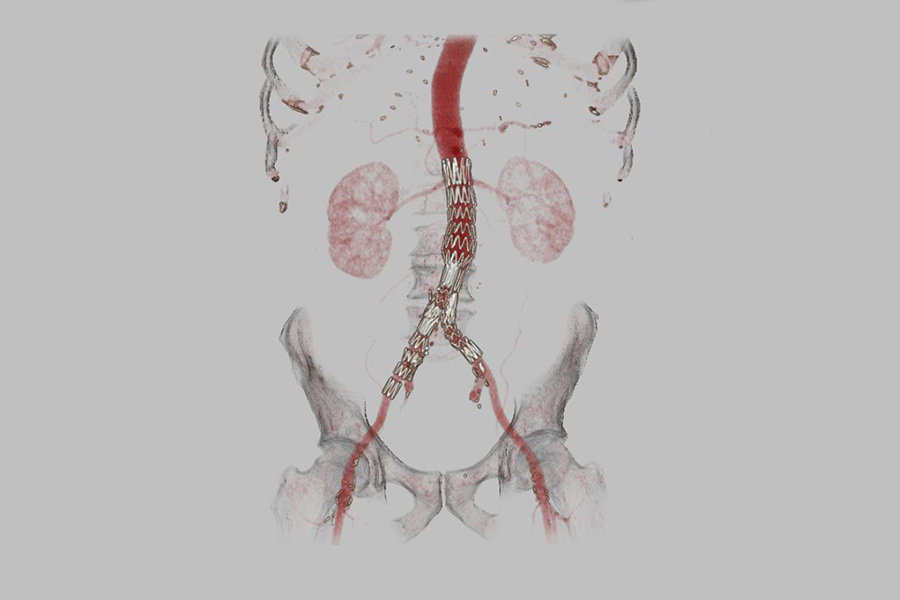

- Untersuchung der Gefäße (CT-Angiographie)

- Untersuchung des Herzens und der Herzkranzgefäße (Kardio-CT und CT-Koronarangiographie)